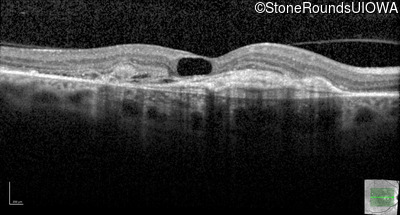

AR Stargardt Disease (IIA)

Age at visit: 59 years (Visit 3)

This 59 year old woman first noticed vision loss in her right eye a few months earlier. She has a cousin with Rhodopsin-associated RP.

Diagnosis & molecular findings

Disease Gene Allele 1 variant(s) Allele 2 variant(s) Inheritance mode

AR Stargardt Disease ABCA4 Arg219Thr AGA>ACA Gly863Ala (G)GA>(G)CA AR